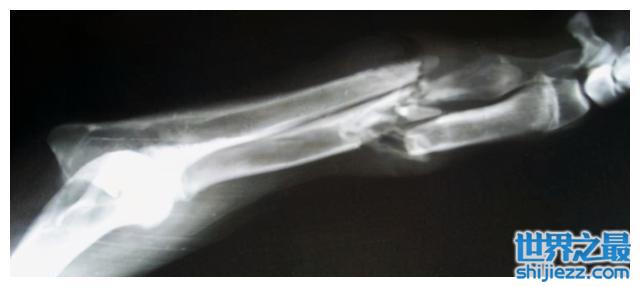

警方又惊奇地发现车里死者身上骨头多处粉碎骨折,由于车辆是翻入沟里,但是沟底距离路面不足1米的距离,车辆翻滚也不至于能使驾驶员多处粉碎骨折,警察确认这属于他杀并放入车里,然后点燃车辆烧毁证据。